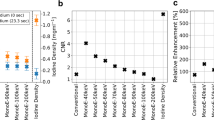

In two animals (=four sections), the septal segment of the left ventricular myocardium had to be excluded from the analysis because of beam-hardening artifacts caused by contrast material passage through the right ventricle. These artifacts resulted in hypo- and hyperdense streak artifacts averting any assessment of the affected myocardium. Thus, 36/40 myocardial segments (90%) were assessable. Visual assessment of MR imaging and MDCT revealed hypo-enhancement defined as myocardial ischemia in the identical 10/36 assessable segments. TTC staining proved the presence of myocardial infarction in these segments (Fig. 3). For MR imaging as well as for MDCT analysis of SImax, the Tmax and slope showed significant differences between normal and infarcted myocardium. For CAT, no significant differences were found. Furthermore, absolute values showed significant differences between MR imaging and MDCT results (P<0.001). Fig. 4 shows time-density/SI curves for MDCT and MR imaging. In detail, results for the semiquantitative analysis of the contrast enhancement are given in Table 1.

Time-density curves for MDCT (a) and time-SI curves for MRI (b) demonstrate missing contrast enhancement in the area of myocardial infarction. Although the curves reflect differences between both imaging modalities, both techniques show an identical contrast enhancement pattern, differentiating normal from infarcted myocardium